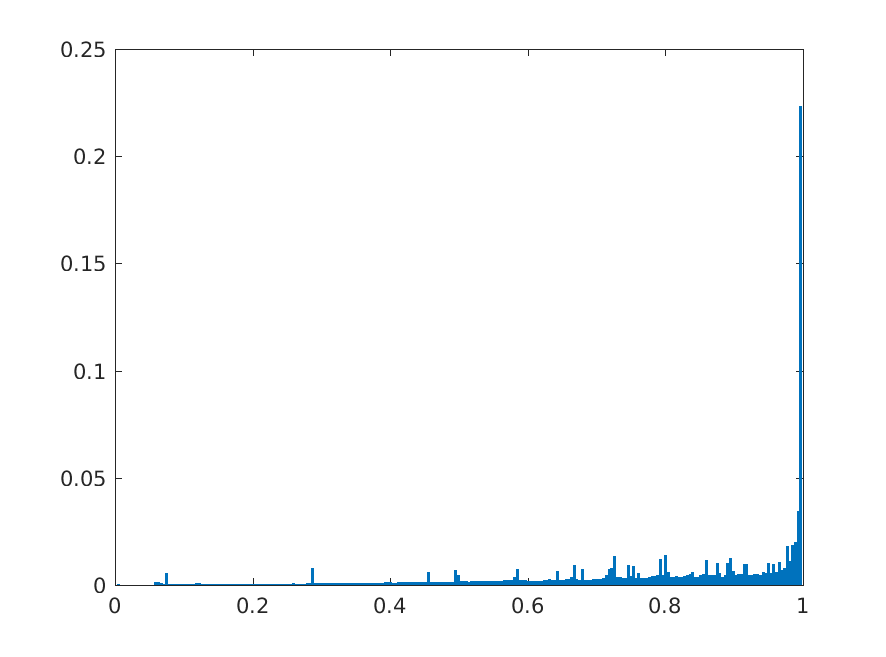

8 Additional Examples of Localization

In this section we show more examples of localization. Few localization samples are shown in Fig. 11. It can be observed that, in the CXRs with Cardiomegaly (Fig. 11(a) and (b)) a fine localization around the heart is observed. In the normal CXRs (Fig. 11(c) and (d)) such localization is not observed. Rather the lowest probabilities are spread out in the CXR image. It is interesting to note that, the localization algorithm gets low probability where the heart is enlarged during cardiomegaly, but the proportion is small compared to the localization in other areas of normal CXRs. In order to observe the performance of the heat map we computed histograms of heat maps of each of the 100 CXRs in the test set for Cardiomegaly detection and average histograms are shown in Fig. 11(e) and (f) for CXRs with Cardiomegaly and normal CXRs, respectively. It is to be noted that, the histograms include both success and failure cases. It can be observed that, for CXRs with Cardiomegaly the classifier is highly sensitive toward Cardiomegaly detection even under occlusion. This indicates that, the classifier primarily looks for local features in a CXR instead of some feature that is spread out in the entire CXR. However, the classifier is not sensitive toward normal CXRs under occlusion. Rather, the probabilities are spread out in the probability spectrum. After that, we analyzed the failure cases where the classifier is unable to classify the image correctly. Two such examples of failure cases are shown in Fig. 12. The localized CXR shown in Fig. 12(a) contains Cardiomegaly whereas the classifier detects it as normal. However, the localization shows that it localizes around heart quite well despite the in accurate classification. On the other hand, Fig. 12(b) shows an example of normal image which has been classified as Cardiomegaly by the classifier. There is stronger localization around the hear that that is observed for normal images as in Fig. 11(c) and (d), however, like those images the localization is spread out.

In a similar fashion, additional localization results for Pulmonary Edema is shown in Fig. 13. In Fig. 13(a) and (b) localization of two examples of CXRs with Pulmonary Edema is shown. As stated earlier the classifier localizes in the lung region. This is not the case when normal images are used to localize Pulmonary Edema as seen in Fig. 13(c) and (d). The localizations are obtained in random dense locations such as the sternum or heart. Like the cardiomegaly case, the histogram averages for CXRs with pulmonary Edema (Fig. 13(e)) shows a sensitivity toward pulmonary edema detection while the normal CXRs shows a spread out detection. It is interesting to note that, in the histogram of normal images high probability (¿0.85) is non-existent, thus ensuring low false positive rate. In the test set none of the normal images have been diagnosed as Pulmonary Edema. The failure cases are shown in Fig. 12. These CXRs are with Pulmonary Edema. However, the localization algorithm shows that one of them localizes in lungs whereas the other one shows a localization pattern similar to that obtained in normal CXRs.